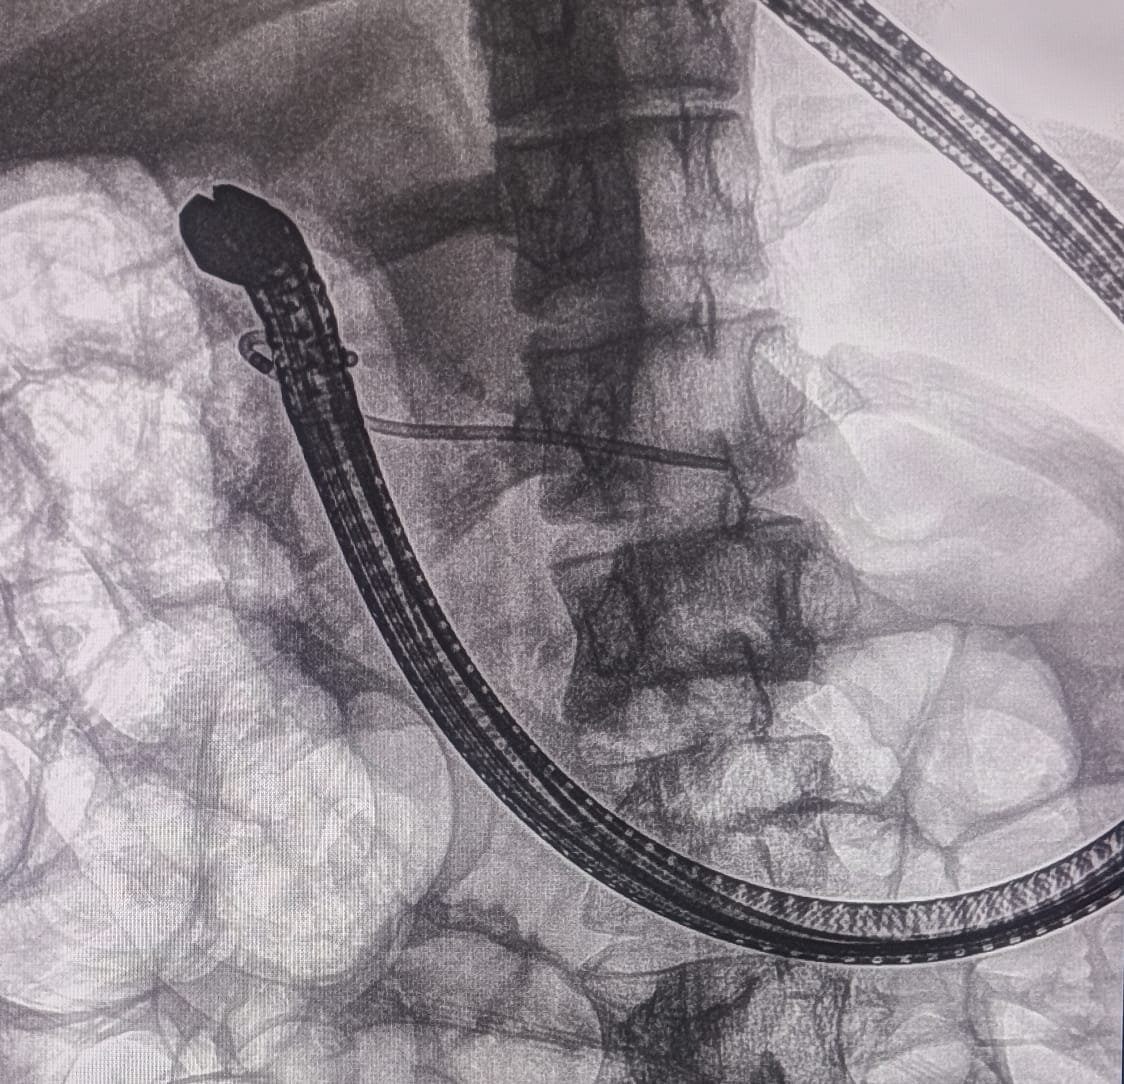

EUS Pancreatogastrostomy was successfully performed. The pancreatic duct was identified and punctured under EUS guidance. A wire was placed into the PD, and the tract was dilated with a 6Fr cystotome. A 10mm x 60mm fully covered metallic SEMS was placed.

A plastic stent was placed inside the metallic stent to stabilize and prevent migration of the metallic stent.

EUS Pancreatogastrostomy Procedure

EUS-guided Pancreatogastrostomy with Stent Placement